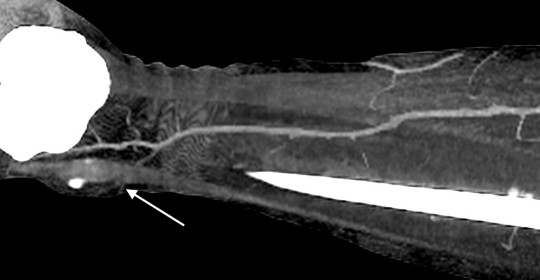

Пацієнти та методи. Відповідно до мети роботи було проаналізовано дані обстеження 46 пацієнтів, що знаходилися на стаціонарному лікуванні в опіковому відділенні КЗ «Дніпропетровська міська клінічна лікарня №2 ДОР» з глибокими локалальними ушкодженнями нижніх кінцівок в період з 2009 по 2015 рік, і яким було виконано 54 оперативних втручань із використанням локальних перфорантних клаптів з живлячою ніжкою, що включала одну домінантну перфорантну артерію. Пацієнти були розділені на дві групи. В групу 1 (контрольну) було включено 25 пацієнтів (29 оперативних втручань) у яких стандартне обстеження включало локацію перфорантів за допомогою аудіо-доплера «Мінідоп» з датчиком 8 MHz. Передбачуване місце вихода перфоранта та його напрямок позначалися на шкірі пацієнта за допомогою маркера [10,12]. (Мал. 1). В групу 2 було включено 21 пацієнта (25 оперативних втручань) у яких стандартне передопераційне обстеження було модифіковане за рахунок контрасної КТ-ангіографії [8,7] з обробкою візуальних карт судинної системи в зоні втручання програмою ”Osirix” (Мал. 2).

Мал. 2. Контрасна КТ-ангіографія з обробкою візуальної карти судинної системи нижньої кінцівки в зоні втручання програмою ”Osirix”. Точку виходу перфрантної артерії в шкіру над кісточкою – відзначено стрілкою.